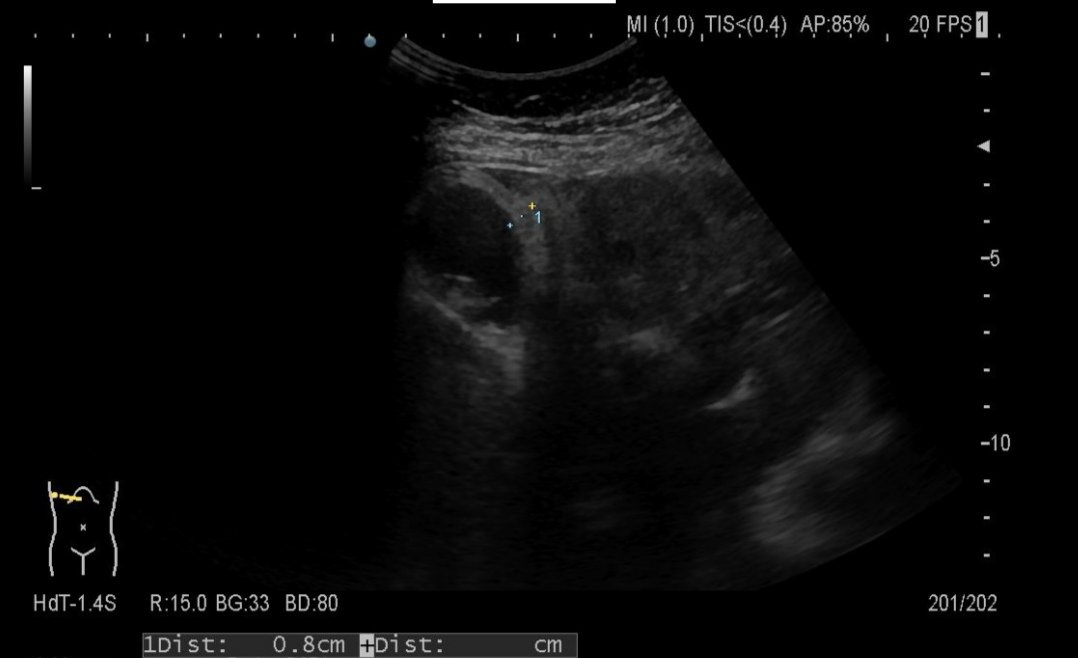

A case of EBV Acute Hepatitis in adulthood.

There are no significant changes in liver echo-texture in acute viral hepatitis.

However, enlarged perihepatic lymph nodes are a fairly constant feature.